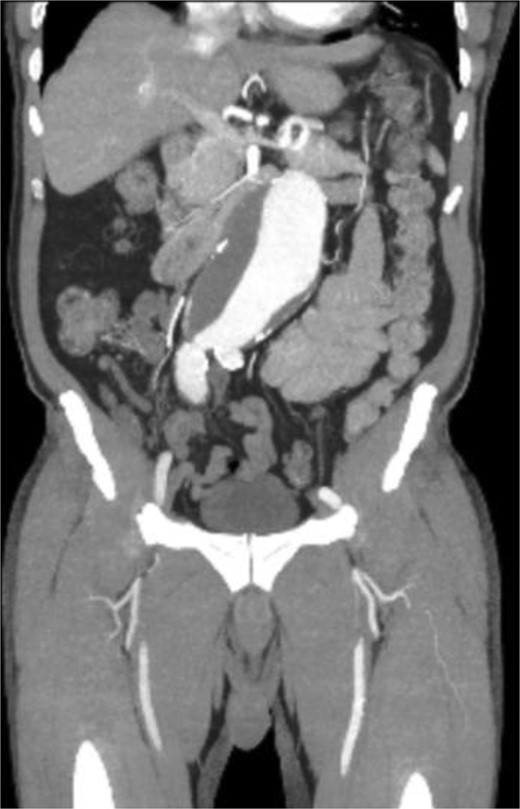

A 71-year-old male with a past medical history of hypertension, dyslipidemia, and renal insufficiency presented to the emergency department with headache and dizziness that began after performing manual labor. The only abnormality with initial vital signs was an elevated blood pressure. Physical exam revealed a palpable pulsatile mass in the epigastrium. An electrocardiogram showed normal sinus rhythm with signs of previous inferior and anterolateral infarcts. Troponin levels were within normal limits. Further workup with an echocardiogram demonstrated left ventricular hypertrophy and ejection fraction (EF) of less than 50%. Due to the pulsatile abdominal mass, a computed tomography (CT) of the abdomen without contrast, and subsequent CT angiogram of the abdomen and pelvis, was completed that demonstrated a 7.1-cm infrarenal AAA with a large mural thrombus causing luminal narrowing (Figs 1 and 2).

CT angiogram of abdominal aorta and iliofemoral artery axial view.

CT angiogram of abdominal aorta and iliofemoral artery coronal view.